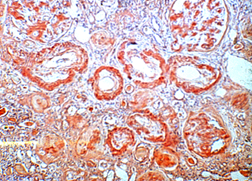

五、 特殊染色

PAS染色、天狼猩红染色、甲苯胺蓝染色、六胺银染色、PAS+萘酚黄S染色、凯氏带染色、VG染色、EVG染色、网状纤维染色、纤维素MSB染色、刚果红染色等。